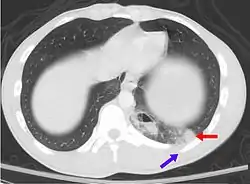

- كدمة رئوية